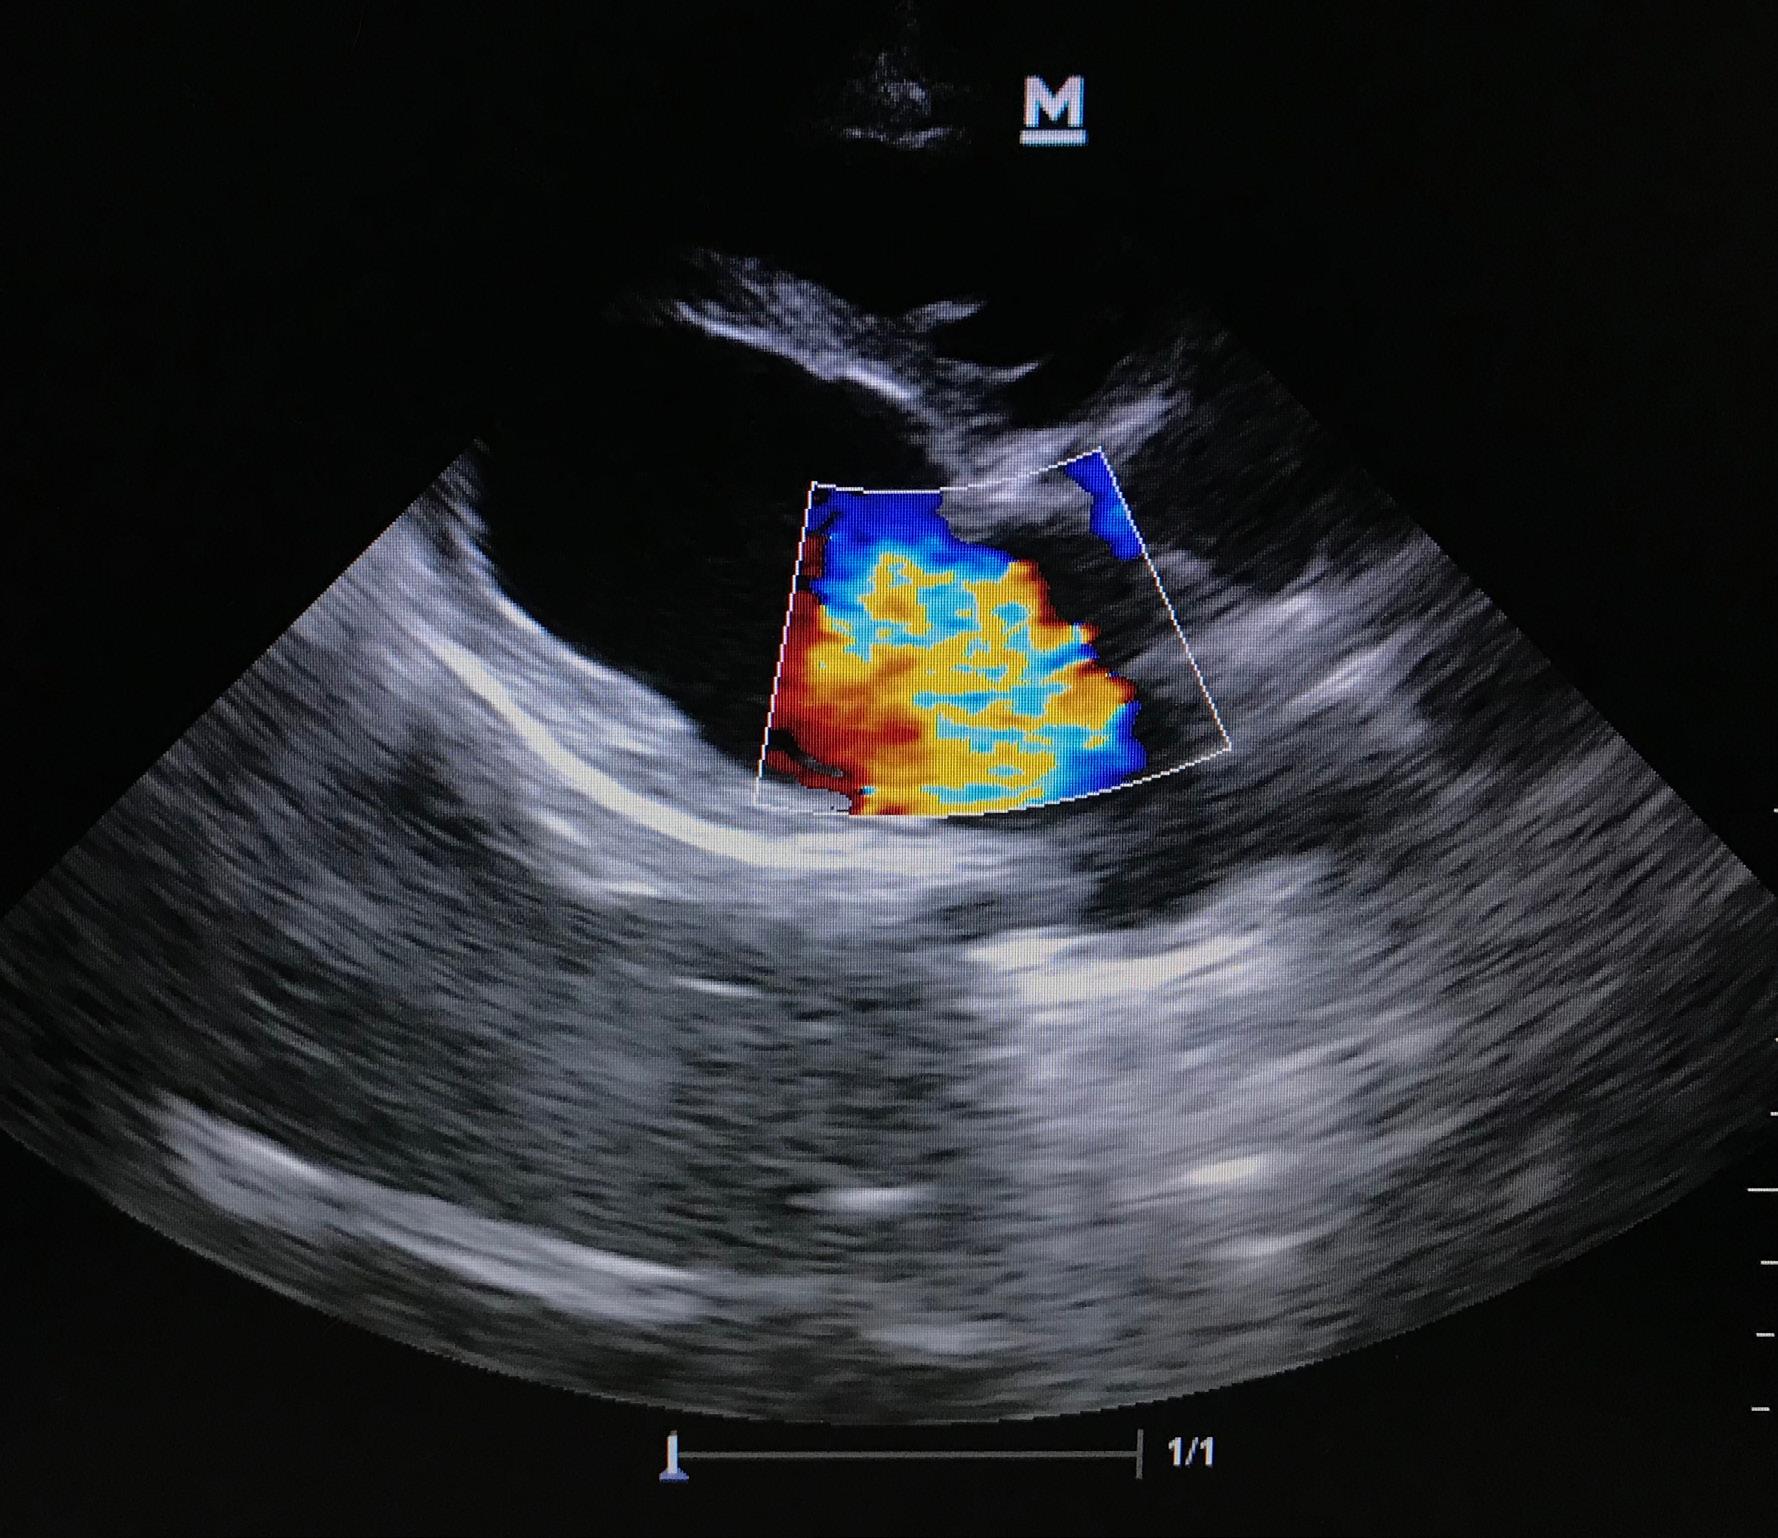

An echocardiogram showing regurgitation of blood through the mitral valve of the heart.

• Echocardiography (ultrasound of the heart): To evaluate

valve function, heart size, and regurgitation severity.